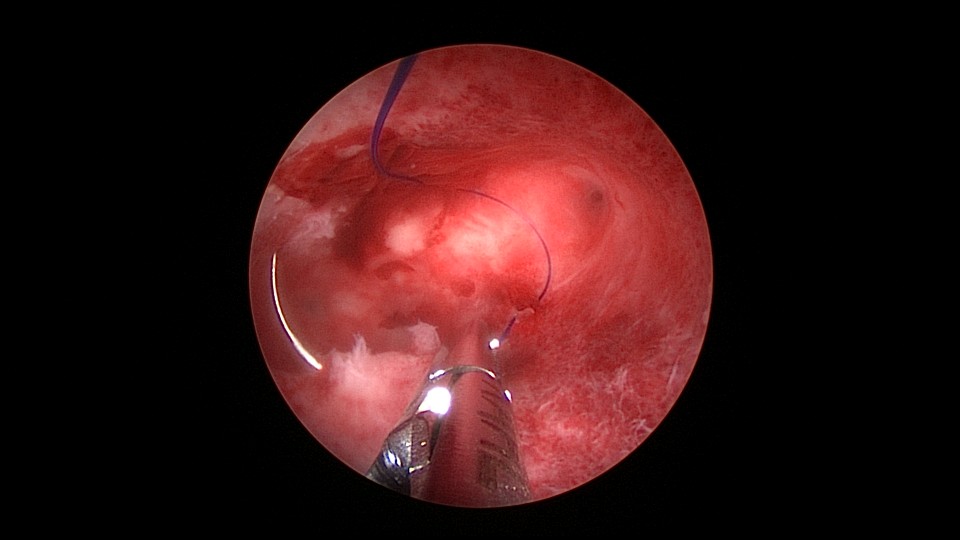

患者39岁,G6P1,顺产1次。2022年5月因输卵管间质部妊娠行宫腹腔镜手术(术前门诊医生诊断宫角妊娠),腹腔镜下行左侧输卵管间质部妊娠套扎开窗取胚术,术中见子宫腺肌症结节明显。2025年3月,严重痛经,皮下注射亮丙瑞林已3个周期,行经第6天,放置曼月乐并固定,拟行缝合固定,宫腔镜下缝合一针,牵拉确认缝合到肌层,推结时缝合处撕裂,拉出曼月乐,立即改为挂钩固定。先将不锈钢挂钩插入宫底肌层,4-0不可吸收线在曼月乐横臂中间套扎形成线圈,将曼月乐置入宫腔,异物钳夹持线圈挂到不锈钢挂钩里,原位固定曼月乐,退出宫腔镜,结束手术。2025年5月复查B超,节育环距宫底3cm,查看图片,线圈较大。节育环距宫底距离跟子宫大小、宫壁厚度、挂钩长度及线圈长度之和有关,保持这个距离不再延长即为手术成功。